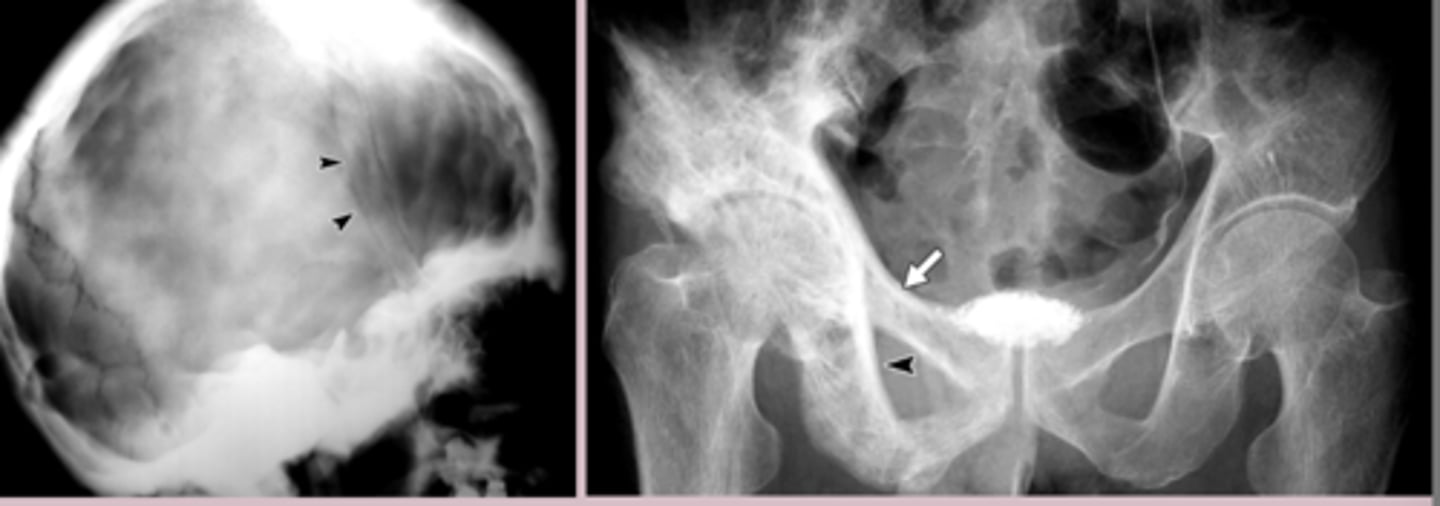

osteoarthritis dx

Imaging

-Xray weight bearing: Asymmetric joint space narrowing

-subchondral sclerosis, osteophytes, subchondral cysts

-Xray: lytic lesions, slcerotic lesions, bone enlargement and deformity